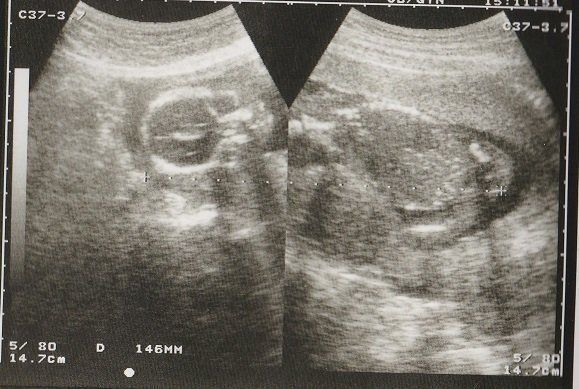

ちゃじゅびさんの妊娠18週目のエコー写真 画像におさまらないほどに成長する

赤ちゃんがどんどん大きくなり、1枚の超音波画像ではおさまりきらなくなりました。画像を2枚くっつけて赤ちゃんの大きさを測っています。

BPD(児頭大横径=頭の直径)を測って、胎児の発育を調べるようです。ここまで、母子ともに特に異常も無く過ごせました。